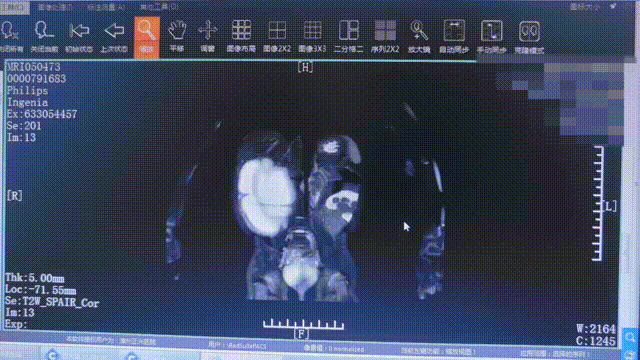

▲ 患兒體內(nèi)囊腫影像(白色部分即為囊腫)

李建國副院長按照術(shù)前規(guī)劃一步步執(zhí)行著器械操作,在實(shí)際探查星星體內(nèi)結(jié)構(gòu)時(shí)驗(yàn)證了自己的猜想:這個(gè)囊性腫塊實(shí)際上屬于肝囊腫。囊腫與內(nèi)臟相距甚微,意味著他必須高度集中精神,不能出任何差錯(cuò)。

李建國副院長依照手術(shù)方案,冷靜、有序地操作著器械,使其將囊液如數(shù)抽出??紤]到假如只是單純實(shí)施這一步驟,星星還會(huì)有再復(fù)發(fā)的可能性,于是他決定將肝囊腫完整去除,再次手術(shù)。

1000ml的囊液,約2斤的重量,李建國副院長歷經(jīng)一個(gè)小時(shí)的攻關(guān),完整地切除了囊腫,成功避免術(shù)后復(fù)發(fā),星星終于得以徹底卸下這個(gè)沉重的“負(fù)擔(dān)”。